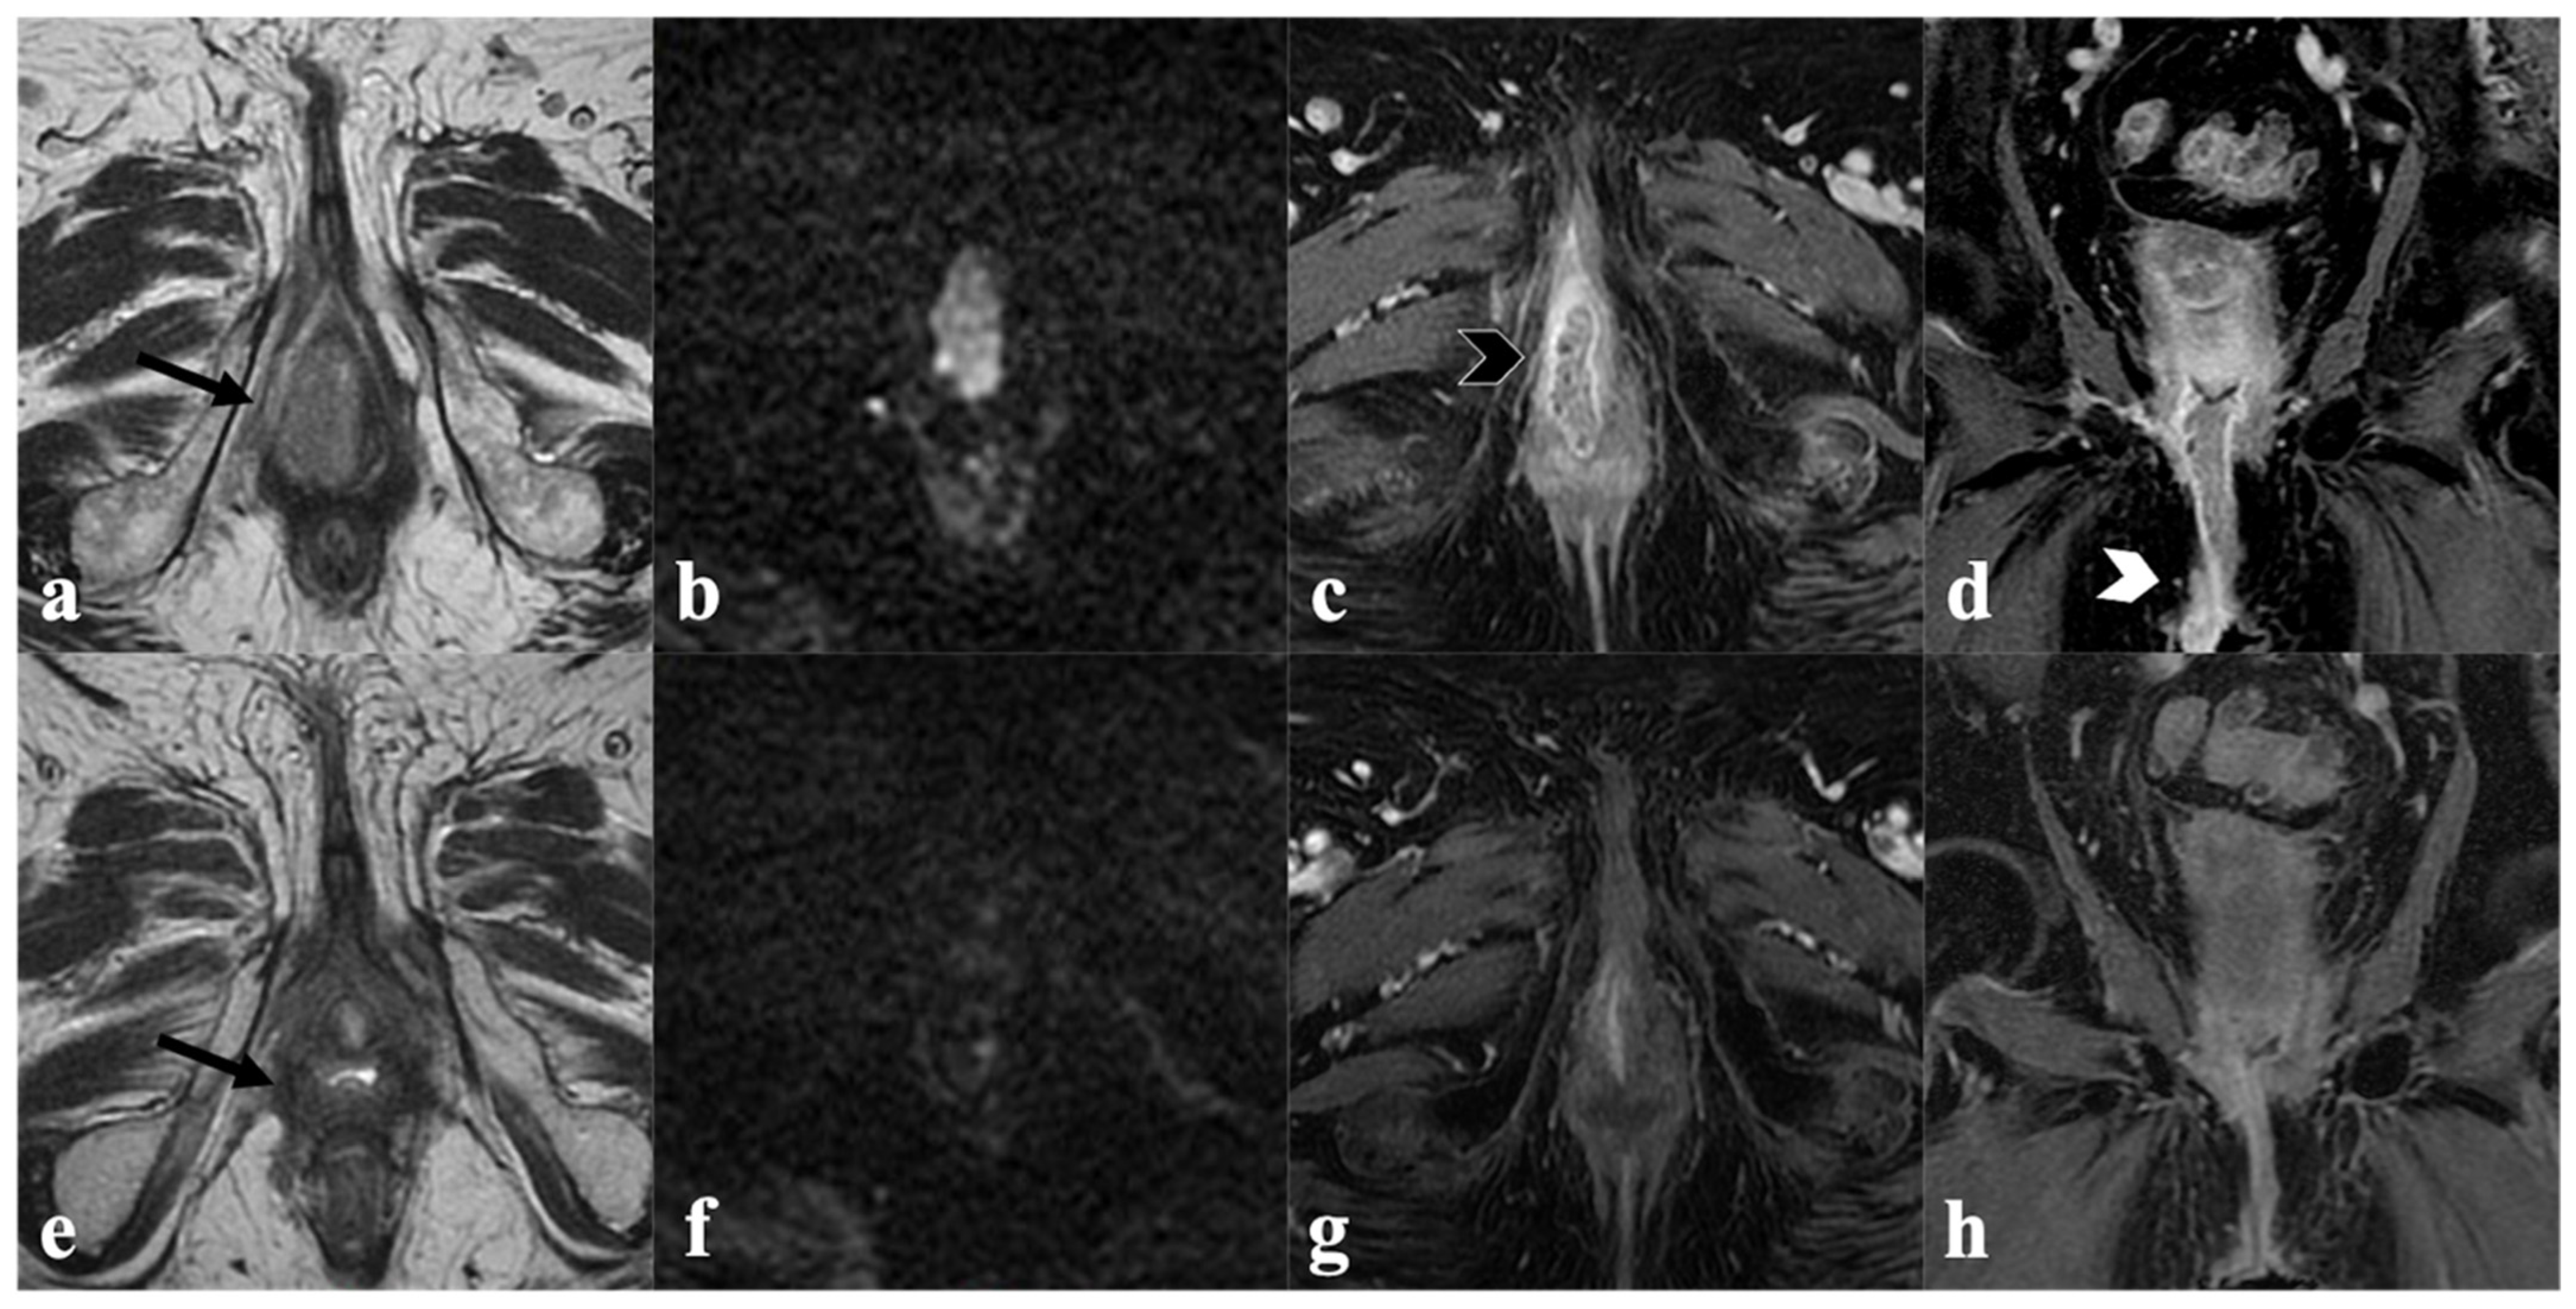

3.2. Urethra

3.3. Anal Sphincter Complex

4. Post-CRT MRI Findings

4.1. Local Tumor Status and Residual Invasion of Adjacent Organs

4.2. Lymph Node Status